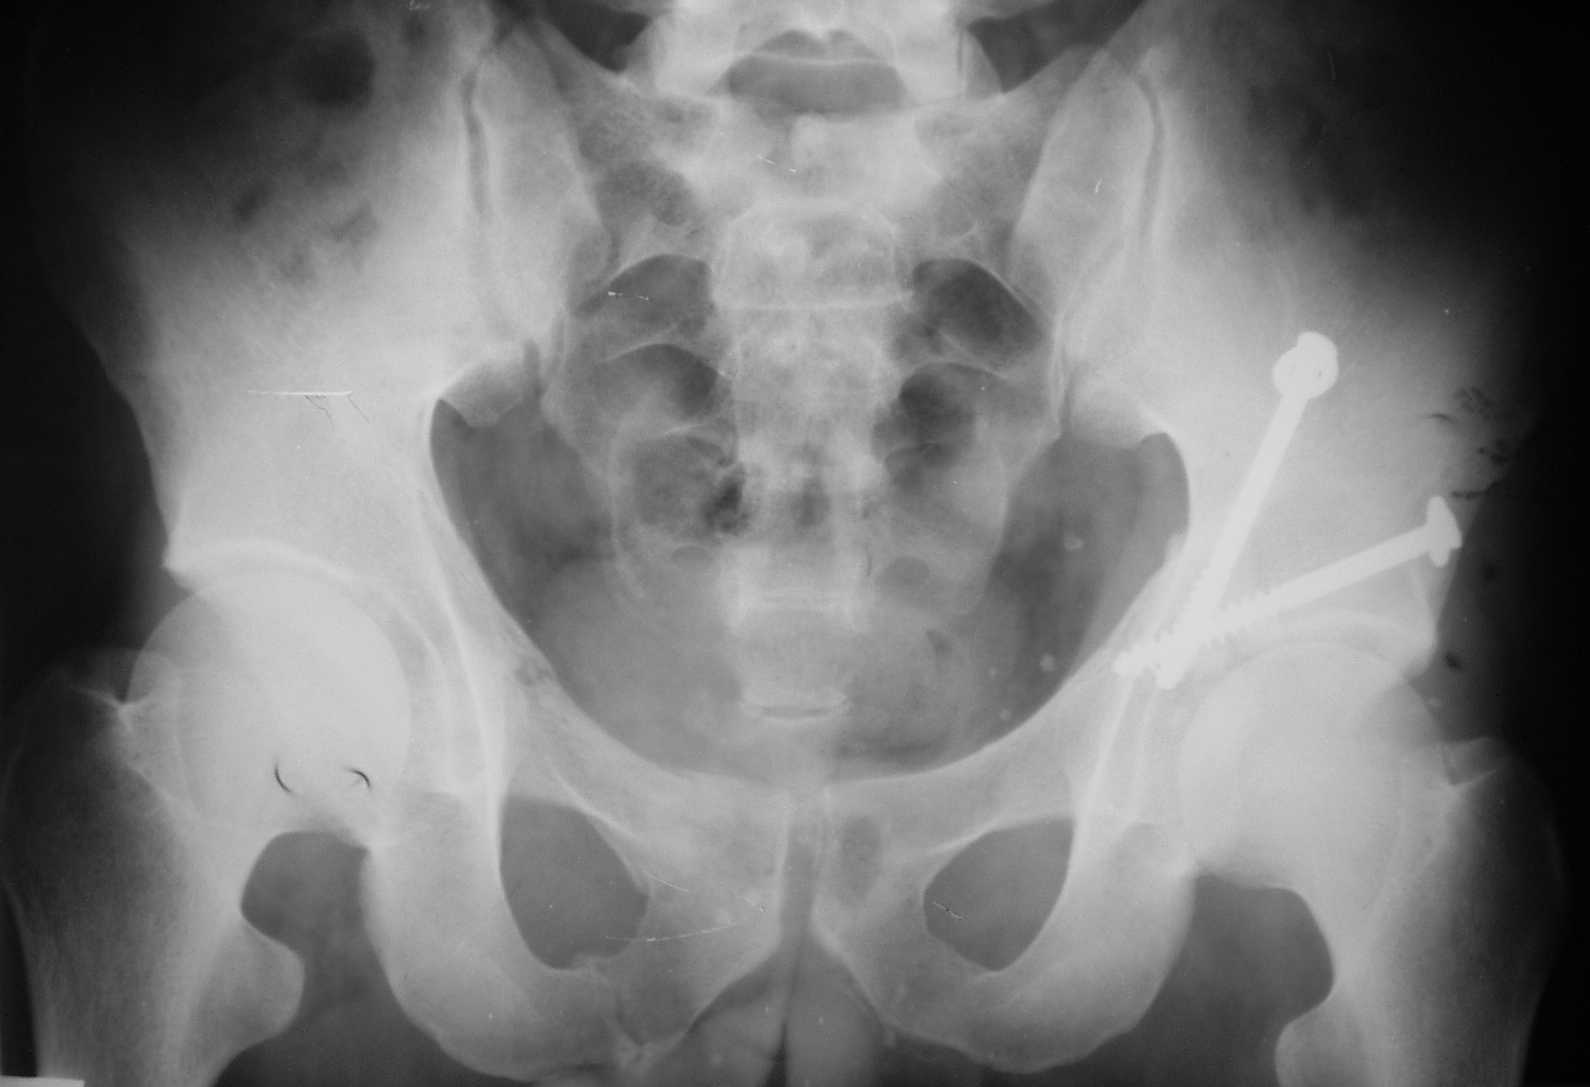

The details of the fracture are not so clear from the images sent...would you be able to send along an AP and Judet images as well as some additional axial images above and below the joint?

I’m not so sure that your patient has a Tr+PW pattern based on the images sent...maybe the fracture’s exact name won’t matter in the long run, but it’d be great to see enough images to make an accurate comment.

Without complete CT images and/or oblique radiographs, it's difficult to answer your question definitively, but it appears that there may not be a posterior wall fracture that requires a posterior approach. A successful reduction through an ilio-inguinal approach will have a faster recovery, and not risk SGN injury or heterotopic ossification.

Here are some more axial images. What is your opinion as for the timing of the operative treatment?